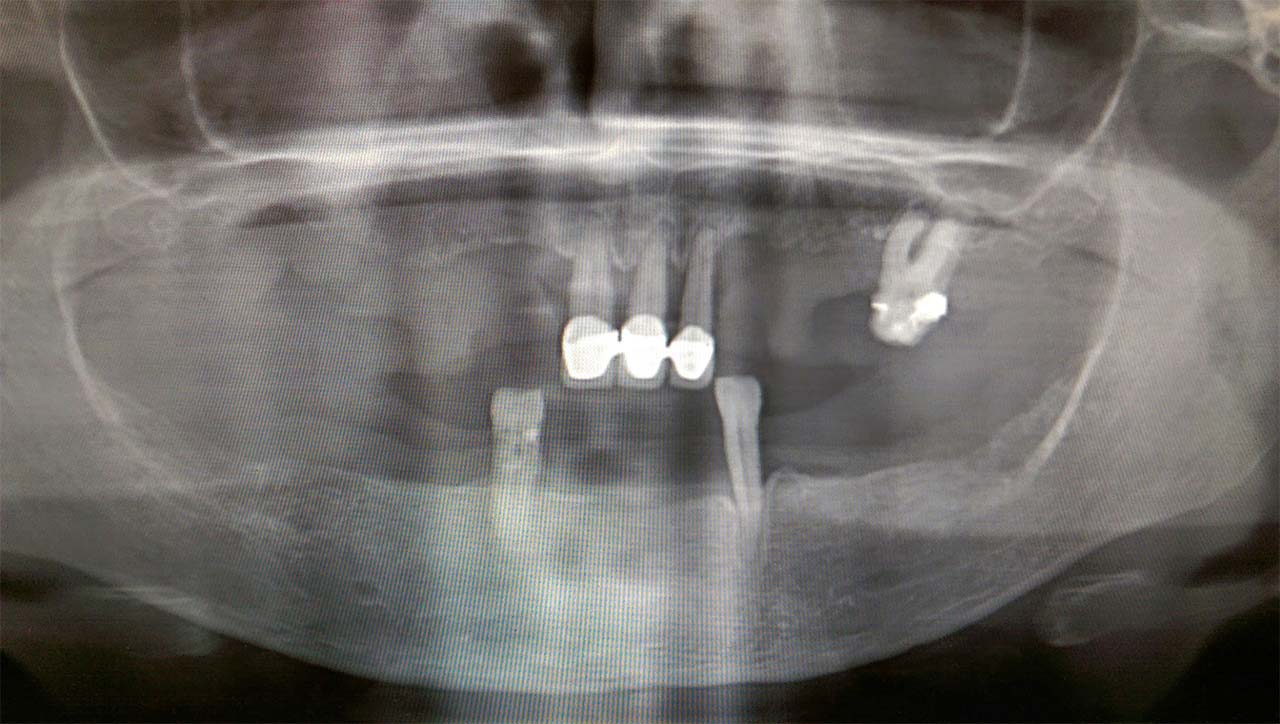

Mitől függ, hogy feltárásban lesz a műtét (vagyis operáció) vagy egyszerű húzás lesz? Ez a fog előtörésének állapotától függ. Teljesen előtört fogaknál nagy az esélye hogy nem kell feltárni. Félig előtört vagy nem előtört fogaknál biztos a feltárás. A fog helyzetéről és a környező anatómiai viszonyokról a fogorvos először panorámaröntgennel tájékozódik.